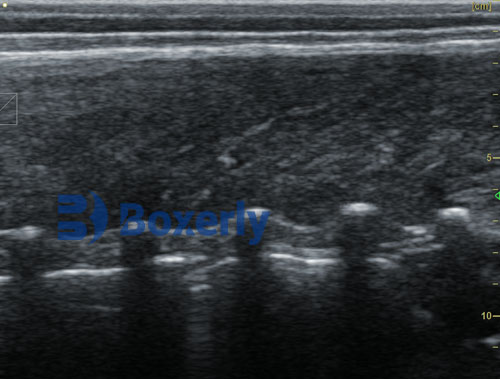

Swine ultrasound devices work by emitting high-frequency sound waves that penetrate tissue and reflect back to create real-time images of internal structures. Portable and rugged ultrasound machines are now commonplace on farms, especially for tasks such as pregnancy detection, fat measurement, and identifying reproductive or uterine issues. These systems are non-invasive, accurate, and repeatable, allowing farmers to make quicker, better decisions without causing stress to the animals.

These measurements are usually taken with B-mode ultrasound machines equipped with linear probes. Devices like the BXL-V50 are specifically designed to provide stable, high-resolution images under field conditions, allowing accurate interpretation by veterinarians or trained technicians.

Real-Time Imaging: B-mode devices show real-time tissue movement and structure, which helps in guiding probe placement and immediate decision-making.